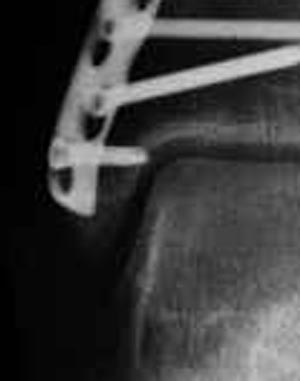

о замедленной консолидации говорить однозначно рано, беспокоиться практически не о чем

Ложка дегтя:

самый дистальный шуруп насквозь через внутреннюю лодыжку в сустав ( см увеличенный рисунок). Хорошо было бы его убрать - стабильности остеосинтезу он совершенно не добавляет.